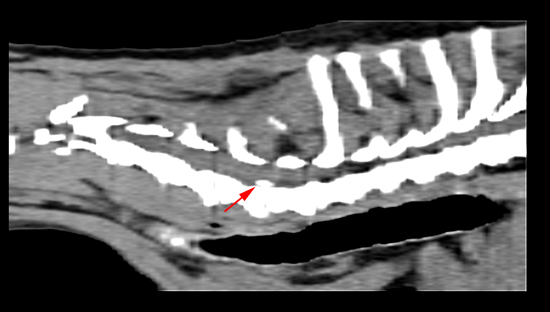

檢查結果發現是第六第七頸椎椎間盤突出壓迫到神經,導致他的左腳麻痺,頸椎也非常疼痛

斷層掃描二